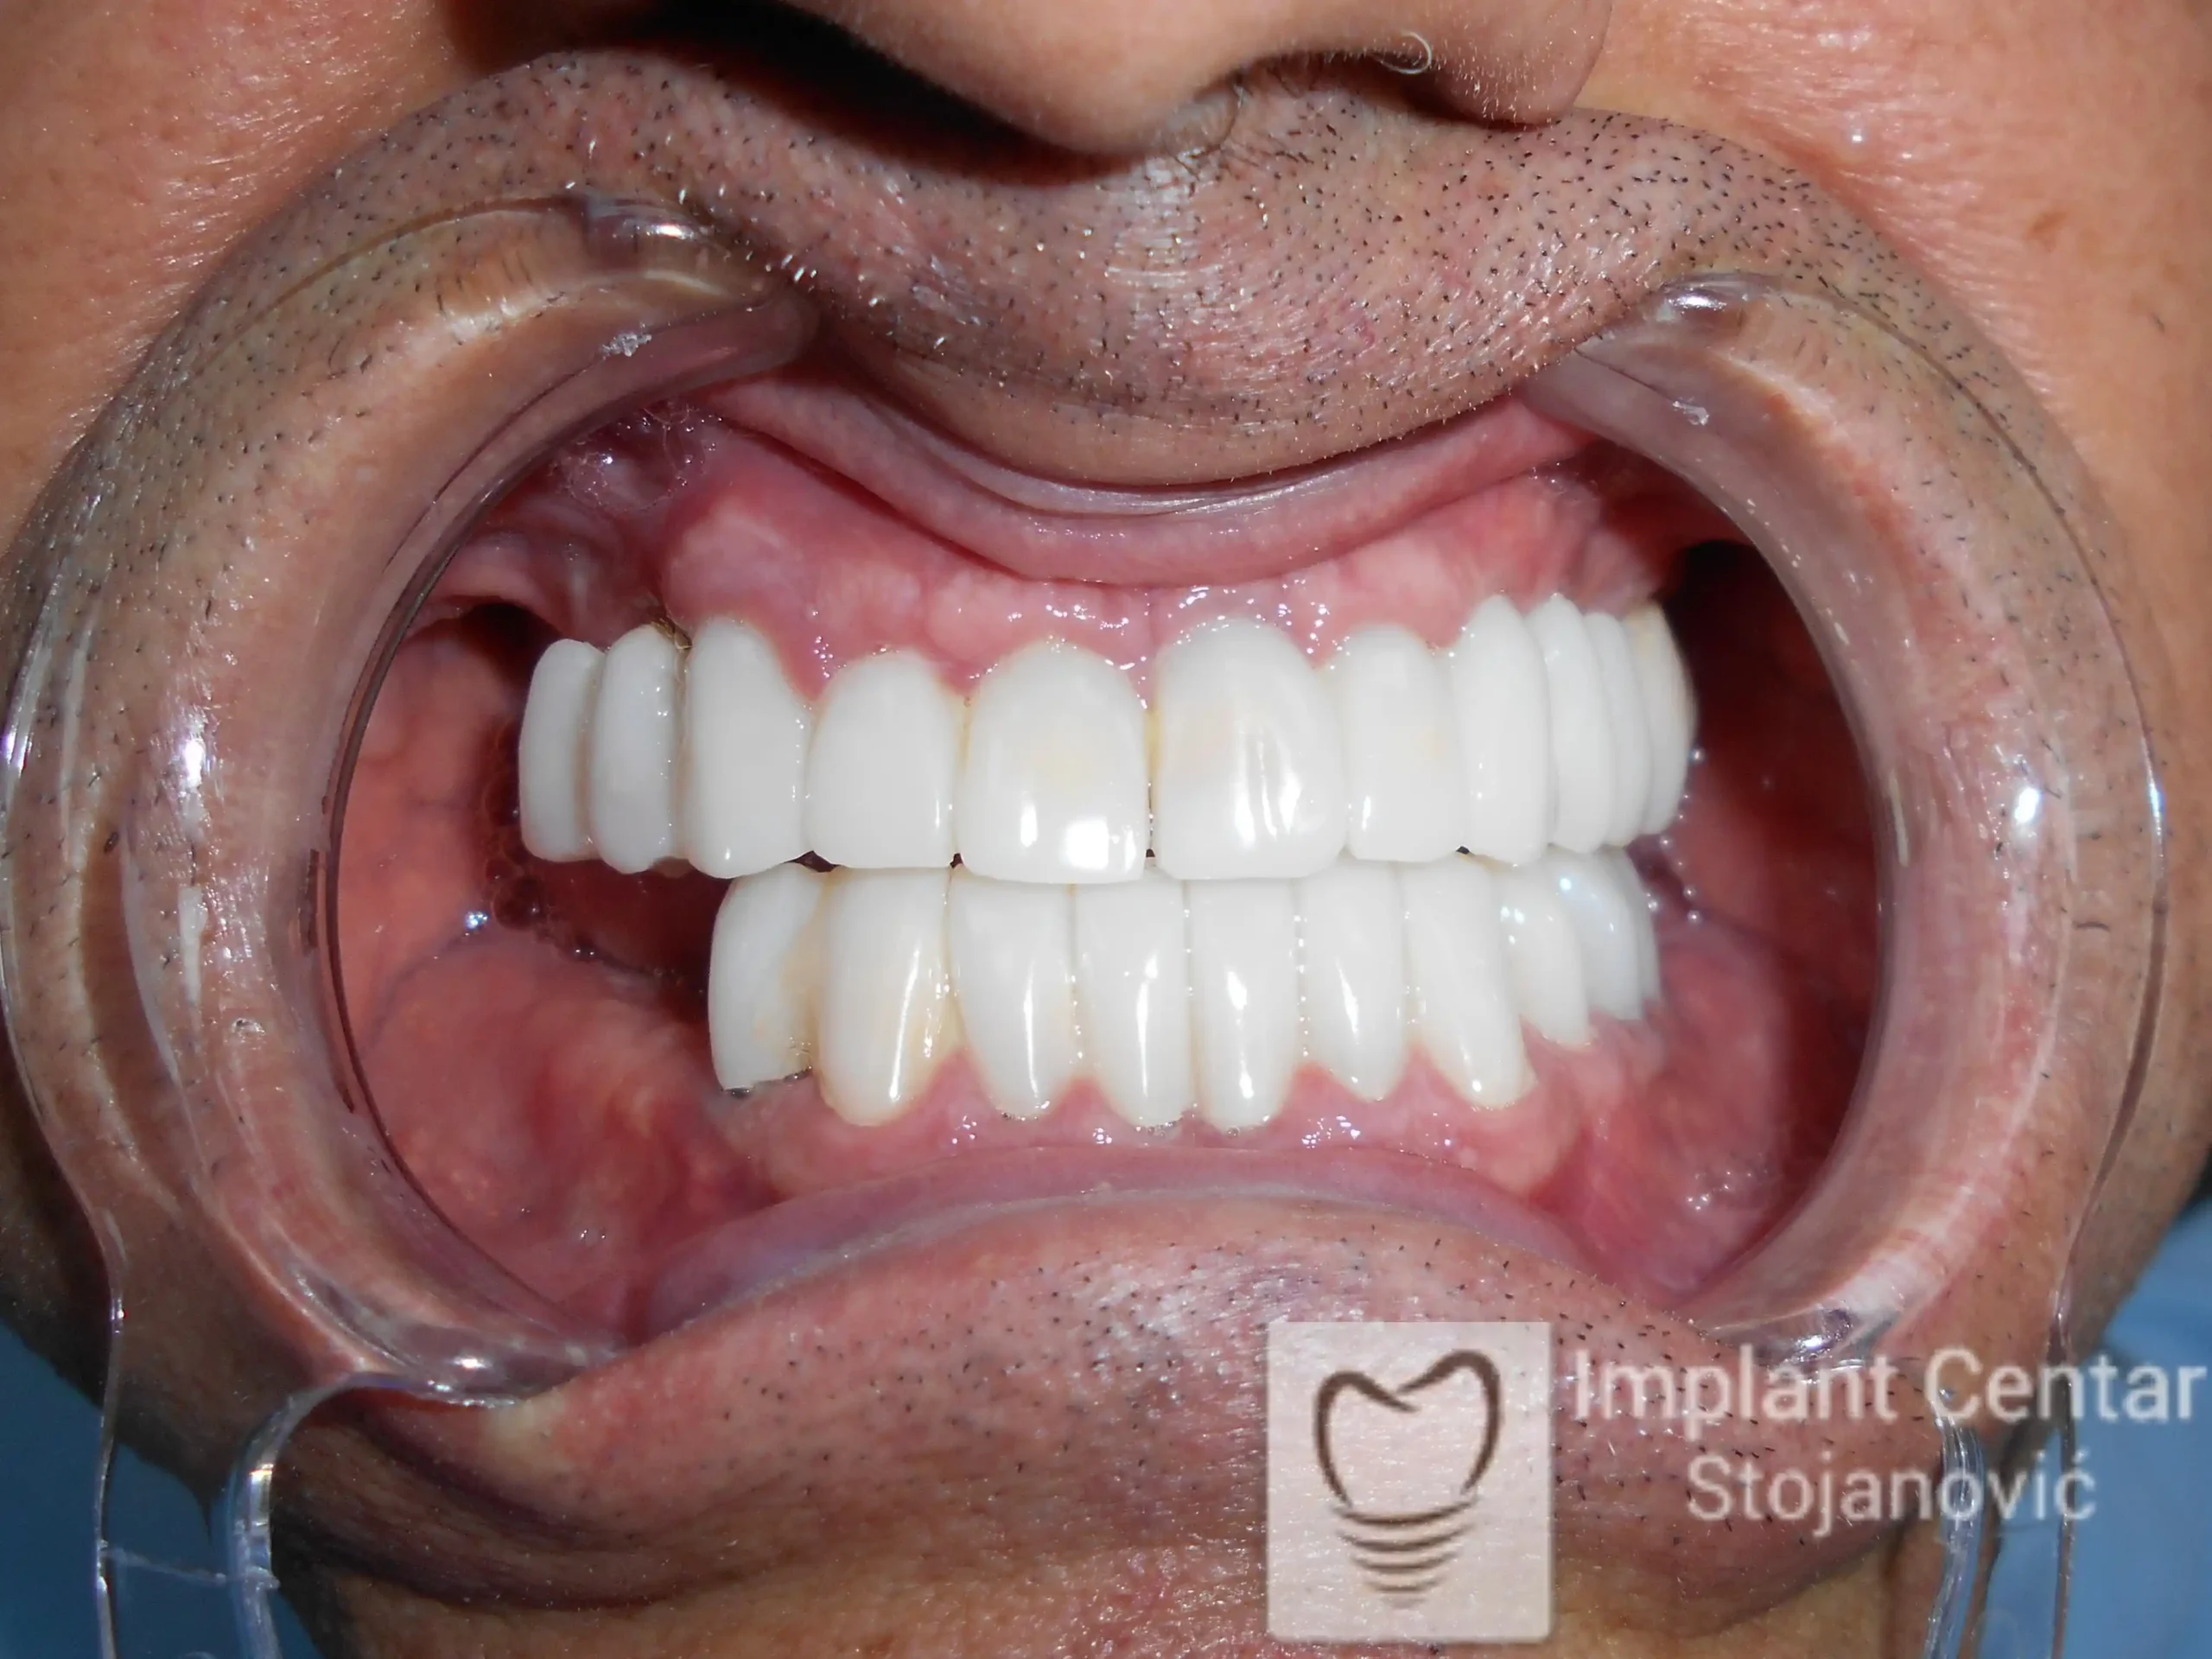

Pacijent sa rascepom usne, nepca i alveolarnog grebena uspešno je rehabilitovan fiksnim protetskim radom na implantatima. Pre dolaska u našu ordinaciju, pacijent je u gornjoj vilici nosio totalnu protezu preko preostalih zuba, dok je u donjoj vilici bio zbrinut parcijalnom mobilnom protezom. Tokom višegodišnje potrage za adekvatnim rešenjem, pacijent nije uspeo da pronađe zadovoljavajuću terapijsku opciju ni u zemlji ni u inostranstvu.

Nakon detaljnog kliničkog pregleda i analize radioloških snimaka, izrađen je sveobuhvatan plan terapije sa ciljem uklanjanja mobilnih proteza i postizanja maksimalne funkcionalne i estetske rehabilitacije. Zbog loše biološke vrednosti preostalih zuba, doneta je odluka o njihovom vađenju i ugradnji dentalnih implantata.

Poseban terapijski izazov predstavljalo je premošćavanje defekta nastalog usled rascepa, kao i ograničena količina raspoložive kosti u gornjoj vilici. Primenom većeg broja implantata i odgovarajućih procedura nadoknade kosti, postignuta je stabilna osnova za fiksni protetski rad.

Tokom perioda oseointegracije, pacijent je bio zbrinut fiksnim privremenim krunicama, čime je već pet dana nakon intervencije obezbeđena potpuna funkcionalna i estetska rehabilitacija. Nakon završetka perioda integracije implantata, izrađeni su definitivni cirkonijum-keramički mostovi na implantatima.

Pacijent je izuzetno zadovoljan postignutim rezultatom, navodeći da po prvi put jasno oseća svoje nepce tokom žvakanja, kao i da se smeje sa punim samopouzdanjem.